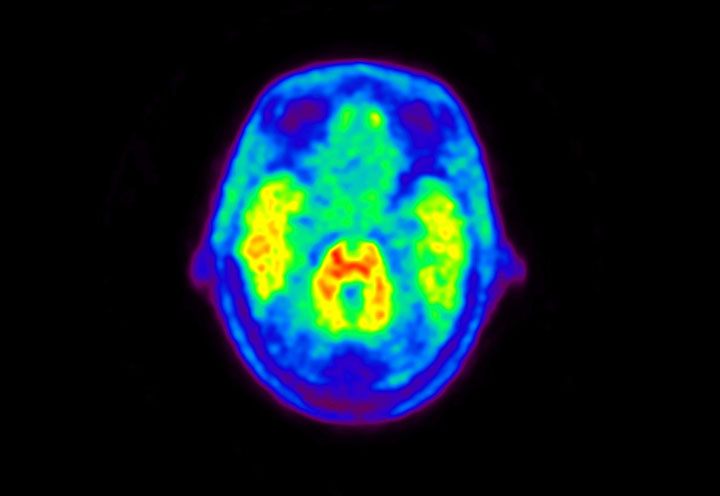

Head / Case5 : Amyloid

Coronal

Courtesy : Kindai University Hospital

- Imaging protocol

- Injected dose: 4.27 MBq/kg, 18F-Flutemetamol

- Uptake time: 99 minutes

- Scan time: 20 minutes